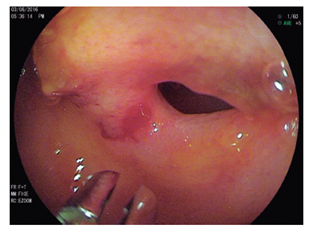

Se realizó una videocápsula endoscópica para el estudio de sospecha de sangrado del intestino delgado, donde se documentó la presencia de estenosis y úlcera localizada en el íleon medio sin sangrado activo (Figura 2). Por estos hallazgos se programó para la realización de una enteroscopia de doble balón por vía retrógrada, donde se evidenció a 190 cm, en forma ascendente a la válvula ileocecal, la presencia de estenosis concéntrica con luz aproximada de 8 mm de diámetro con ulceración en su borde libre sin sangrado, cubierta de fibrina, no franqueable (Figura 3). Durante la enteroscopia, se tomaron biopsias de la estenosis y se realizó un habón submucoso con abundante solución salina, posteriormente se marcó este punto a 3 cm distal al sitio de la estenosis con tinta china para facilitar su localización.